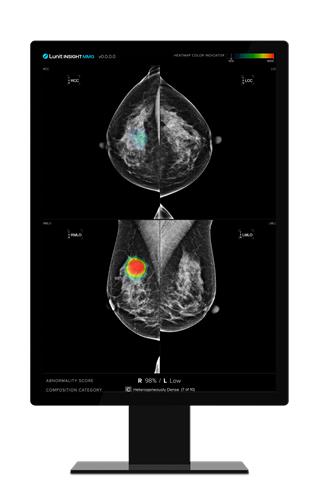

(서울=연합뉴스) 조현영 기자 = 의료 인공지능(AI) 기업 루닛[328130]은 유방촬영술 AI 영상분석 설루션 '루닛 인사이트 MMG'를 사용했을 때 의료진의 업무량이 약 70% 줄어든다는 연구 결과를 확인했다고 8일 밝혔다.

그 결과 유방암 검진 과정에서 루닛 인사이트 MMG를 환자 분류 도구로 도입하면 의료진의 업무량이 69.5% 줄어들고 분류 정확도는 약 30.5% 증가하는 것으로 나타났다.

또 기존 검진에서 놓친 암의 약 50%를 식별할 수 있었고, 검진과 검진 사이에 발생하는 '간격암'의 약 52%도 잡아냈다.

유방촬영술 검사 가운데 영상의학과 전문의 2명이 참여하는 이중 판독 상황에서도 의사 1명 대신 AI를 활용했더니 전체 유방암 환자의 약 23%를 평균 약 30개월 더 빠르게 진단했다.